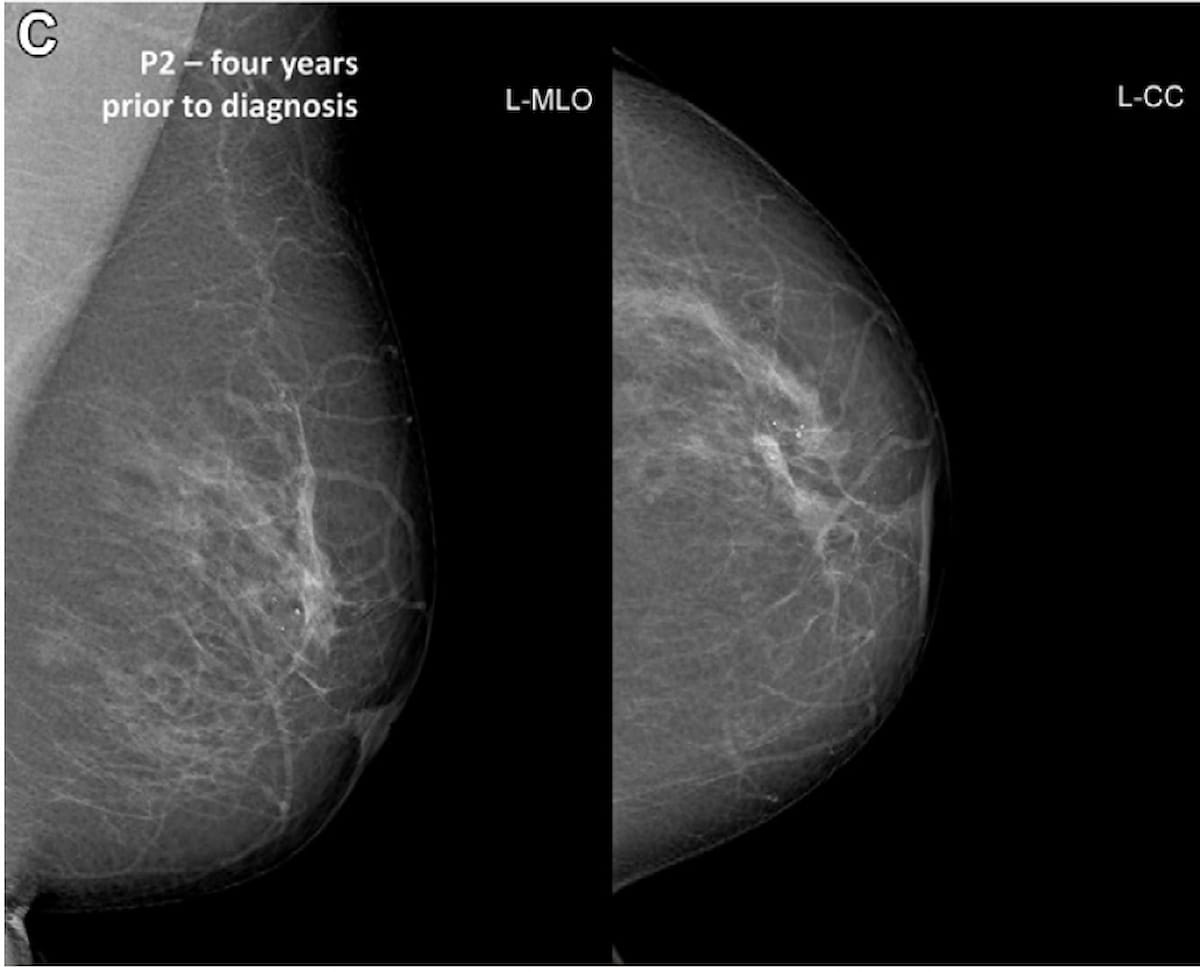

Ici, on peut voir des vues mammographiques des images crânio-caudales gauche (à droite) et oblique latérale gauche (à gauche) prises quatre ans avant le diagnostic de cancer du sein invasif chez une femme de 57 ans. Le système de notation de l’intelligence artificielle (IA) a indiqué un risque élevé de cancer (score AI 10) avec ces images, lors des mammographies de dépistage 2 ans avant le diagnostic et avec les mammographies détectant le cancer du sein. (Photos gracieuseté de Rayons X.)

« …Nous avons constaté que plus d’un cas de cancer sur trois détecté par le dépistage et que le cancer présentait un score de risque d’intelligence artificielle (IA) de 10 au pré-dépistage. » Cela indique la capacité de l’IA à détecter le cancer du sein à un stade précoce, ce qui peut conduire à un traitement moins nocif pour les patients concernés », a écrit le co-auteur de l’étude Solveig Hofvind, Ph.D., affilié à la Division du dépistage du cancer du sein du Registre du cancer de Norvège et professeur de radiographie à l’École des sciences appliquées de l’Université. d’Oslo et d’Akershus, à Oslo, en Norvège, et ses collègues.

Les auteurs de l’étude ont également noté que 23 pour cent des cas de cancer du sein détectés et 23,4 pour cent des cas de cancer du sein d’intervalle ont été identifiés comme présentant un risque élevé de malignité lors des mammographies réalisées quatre ans avant le diagnostic.

Comparativement aux femmes présentant des scores d’IA à faible risque compris entre 1 et 7 dans le groupe du cancer du sein détecté par dépistage, les chercheurs ont noté que les calcifications seules ou la combinaison de calcifications et de densité mammaire étaient plus répandues chez les femmes présentant des scores d’IA à haut risque. .

Pour les mammographies réalisées jusqu’à 2 ans avant le diagnostic de cancer détecté au dépistage, une densité avec calcifications a été observée chez 13,6% des patientes avec un score AI de 10 contre 4,7% des patientes avec un score AI de 1 à 7. Les chercheurs ont constaté que 15,8 % des patients présentant des scores d’IA à haut risque n’avaient que des calcifications, contre 7,8 % de ceux ayant des scores d’IA à faible risque.

« Il peut être important de rappeler les femmes présentant des calcifications qui obtiennent un score de 10 pour évaluation, car cela peut conduire à une détection précoce de cancers associés », ont noté Hovind et ses collègues. « Cependant, la proportion de calcifications et un score AI de 10 devraient également être étudiés chez les femmes indemnes de maladie, car ils peuvent influencer le taux de résultats de dépistage faussement positifs (appelés résultat négatif). »